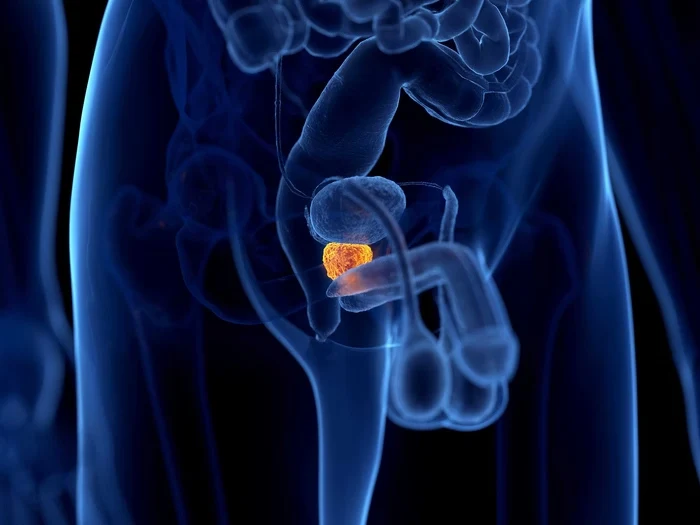

A hiperplasia prostática benigna (HPB) é o aumento não canceroso da próstata que afeta a maioria dos homens após os 50 anos. Este crescimento natural da glândula prostática pode comprimir a uretra, causando diversos sintomas urinários que impactam significativamente a qualidade de vida masculina.

A condição afeta mais de 80% dos homens acima de 80 anos e pode causar sintomas como jato urinário fraco, dificuldade para iniciar a micção, sensação de esvaziamento incompleto da bexiga, urgência urinária, aumento da frequência urinária diurna e noturna, e gotejamento pós-miccional.

O HoLEP está indicado para homens com sintomas moderados a severos de HPB que não respondem adequadamente ao tratamento medicamentoso. É especialmente benéfico para pacientes com próstatas grandes (acima de 80g), onde outras técnicas podem ser limitadas ou menos eficazes.